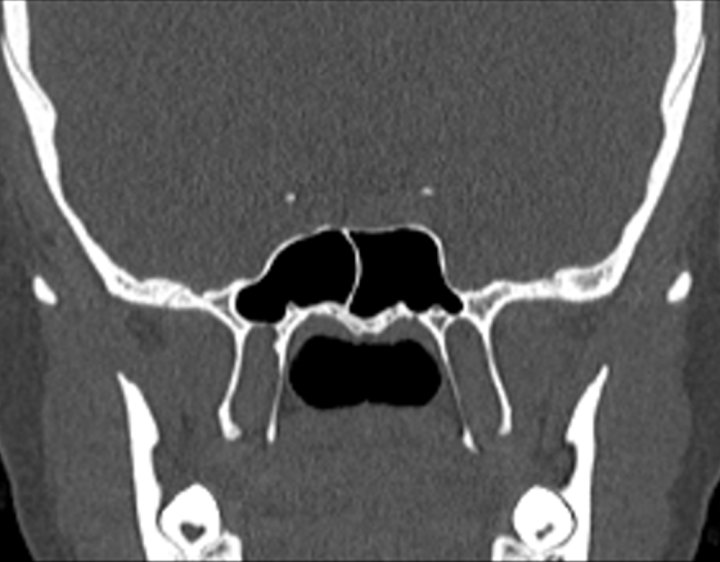

Click any image for labels.